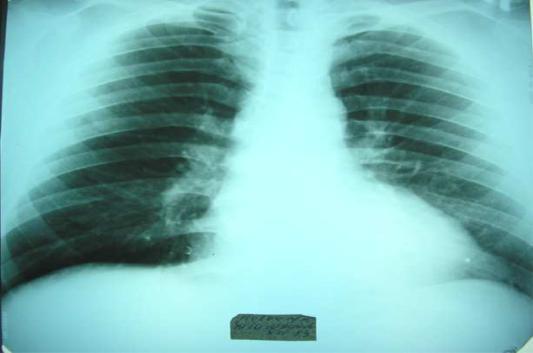

On the heart percussion its dullness enlargement to the left and upwards due to left atrium and left ventricle dilatation is revealed. The heart acquires mitral configuration with smoothed cardiac waist. On right ventricle hypertrophy cardiac dullness also shifts to the right (Fig. 8,9).

Fig.8. Radiography of t he chest in combined heart defect shows mitral configuration of the heart.

Fig.9. Mitral configuration II of the hea rt.